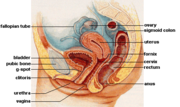

| 2. 12. 2011, 21:23 | Zensky reprodukcni system.png (soubor) |  | 37 kB | Webmaster | (Zdroj: http://commons.wikimedia.org/wiki/File:Female_reproductive_system_lateral.png) | 1 |